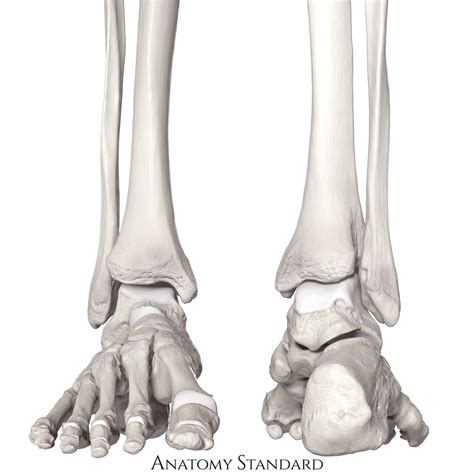

The tibia and fibula are the two long bones that make up the lower leg. The tibia, also known as the shinbone, is the larger and stronger of the two. It bears most of the body's weight and is crucial for standing and walking. The fibula, on the other hand, is thinner and runs parallel to the tibia on the outer side of the leg. It provides stability and serves as an attachment point for muscles and ligaments.

Structure of the Tibia

The tibia has several distinct parts:

• Proximal End: This includes the medial condyle, lateral condyle, and the tibial tuberosity, which is the site of attachment for the patellar tendon.

• Shaft: The long, cylindrical portion of the bone that provides structural support.

• Distal End: This includes the medial malleolus, which forms the inner ankle bone, and the lateral malleolus, which is part of the fibula.

Structure of the Fibula

The fibula also has key structural components:

• Proximal End: This includes the head of the fibula, which articulates with the tibia.

• Shaft: The long, slender portion of the bone.

• Distal End: This includes the lateral malleolus, which forms the outer ankle bone.

Tibia and Fibula Anatomy